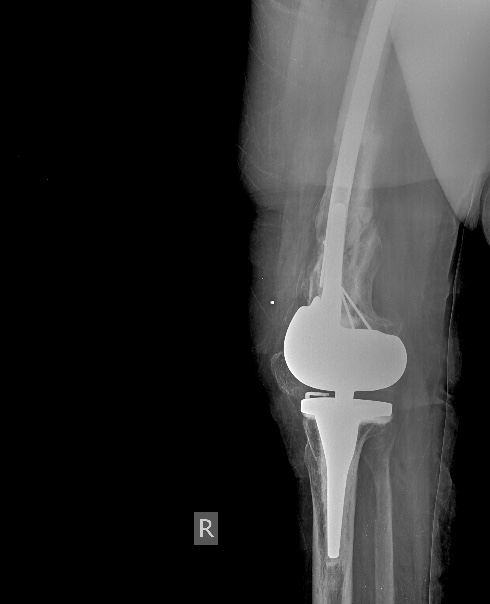

[Ortho] Перипротезный перелом бедра у ребёнка

Оптимальное решение - закрытый остеосинтез интерамедуллярным стержнем с

удлинением ножки эндопротеза. Пример в приложении. Делает такие стержни

предприятие ЦИТО.

Имя     : Бедро AP.0001.jpg